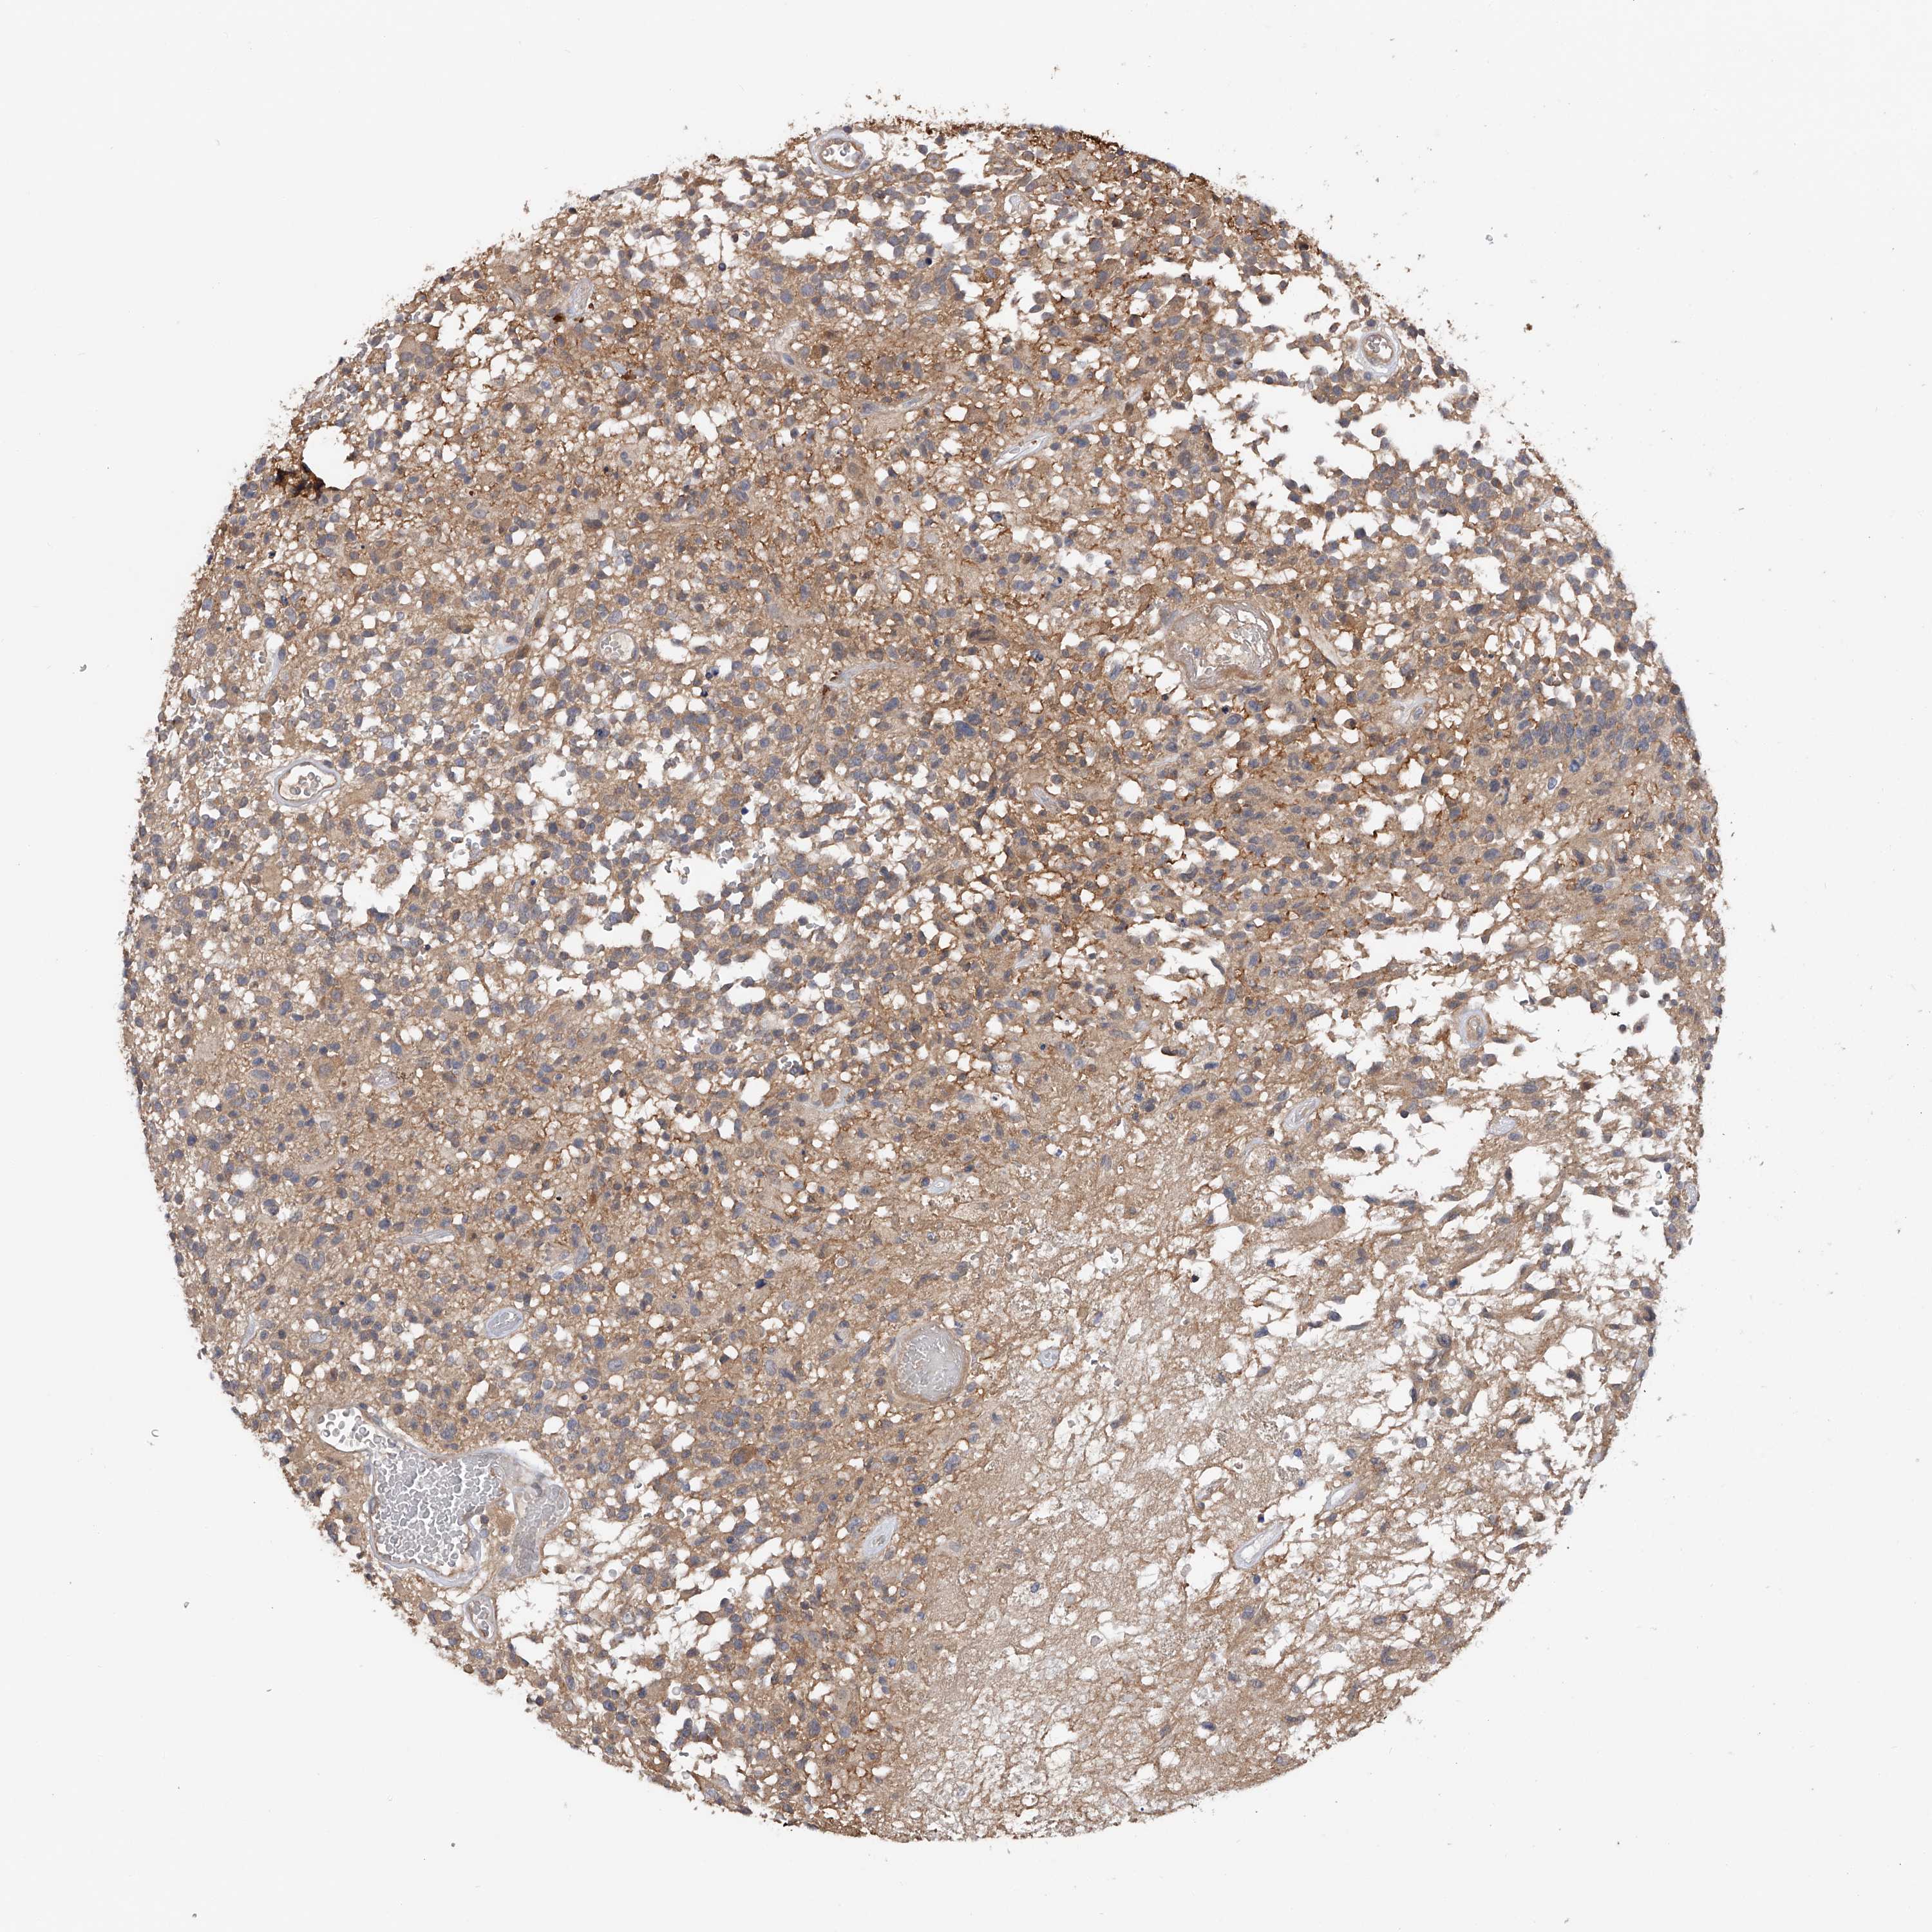

GLIOMA - Protein expressioni

A mouse-over function shows sample information and annotation data. Click on an image to view it in a full screen mode. Samples can be filtered based on level of antibody staining by selecting one or several of the following categories: high, medium, low and not detected. The assay and annotation is described here.

Note that samples used for immunohistochemistry by the Human Protein Atlas do not correspond to samples in the TCGA dataset.

Antibody stainingi

Antibody staining in the annotated cell types in the current human tissue is reported as not detected, low, medium, or high, based on conventional immunohistochemistry profiling in selected tissues. This score is based on the combination of the staining intensity and fraction of stained cells.

Each image is clickable and will lead to virtual microscopy that enables deeper exploration of all samples and also displays staining intensity scores, fraction scores and subcellular localization as well as patient and tissue information for each sample.

Antibody HPA018453

Antibody HPA019055

Antibody HPA028849

Antibody CAB034170

Glioma, malignant, High grade

Glioma, malignant, Low grade

Glioblastoma, NOS